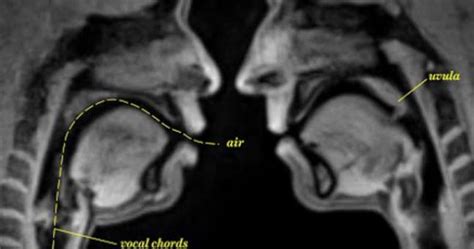

This Is What It Looks Like When You Have Sex In An Mri Machine